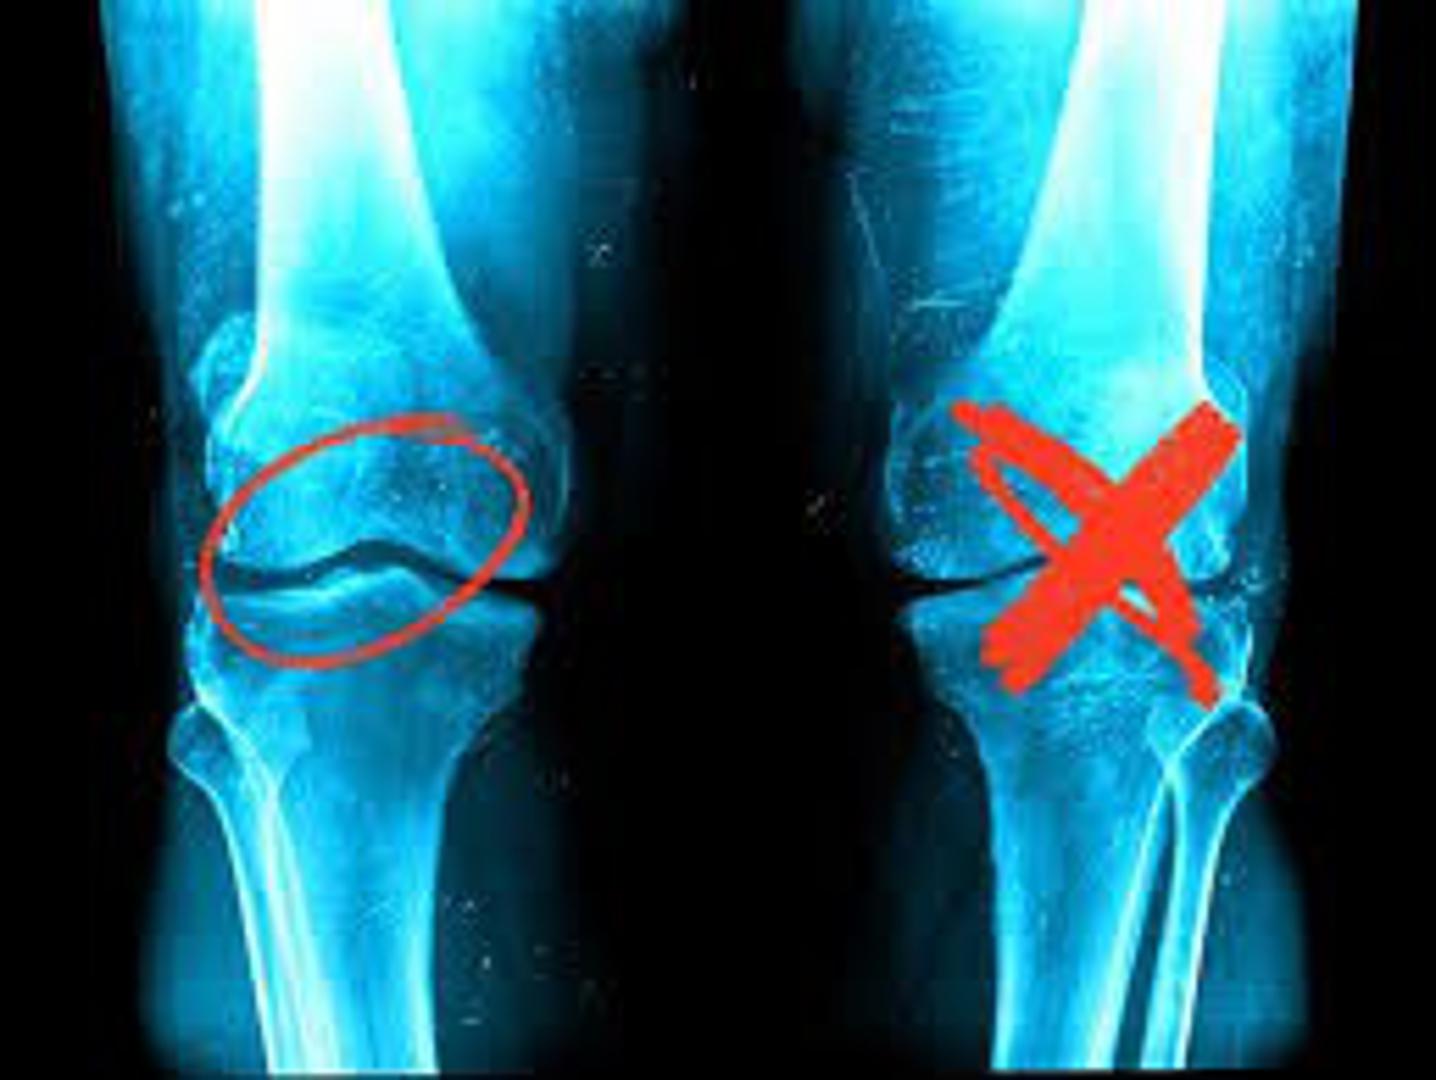

Ako imate slomljene kosti, pokidane tetive ili uvrnute zglobne čahure - potrebna vam je hitna kirurška intervencija. No, ako se borite s bolovima uzrokovanim artrozom, bolestima zglobova, mišićima ili leđima, nubi terapija magnetskim kamenjem je za vas. Njihovi su učinci jednostavno nevjerojatni.